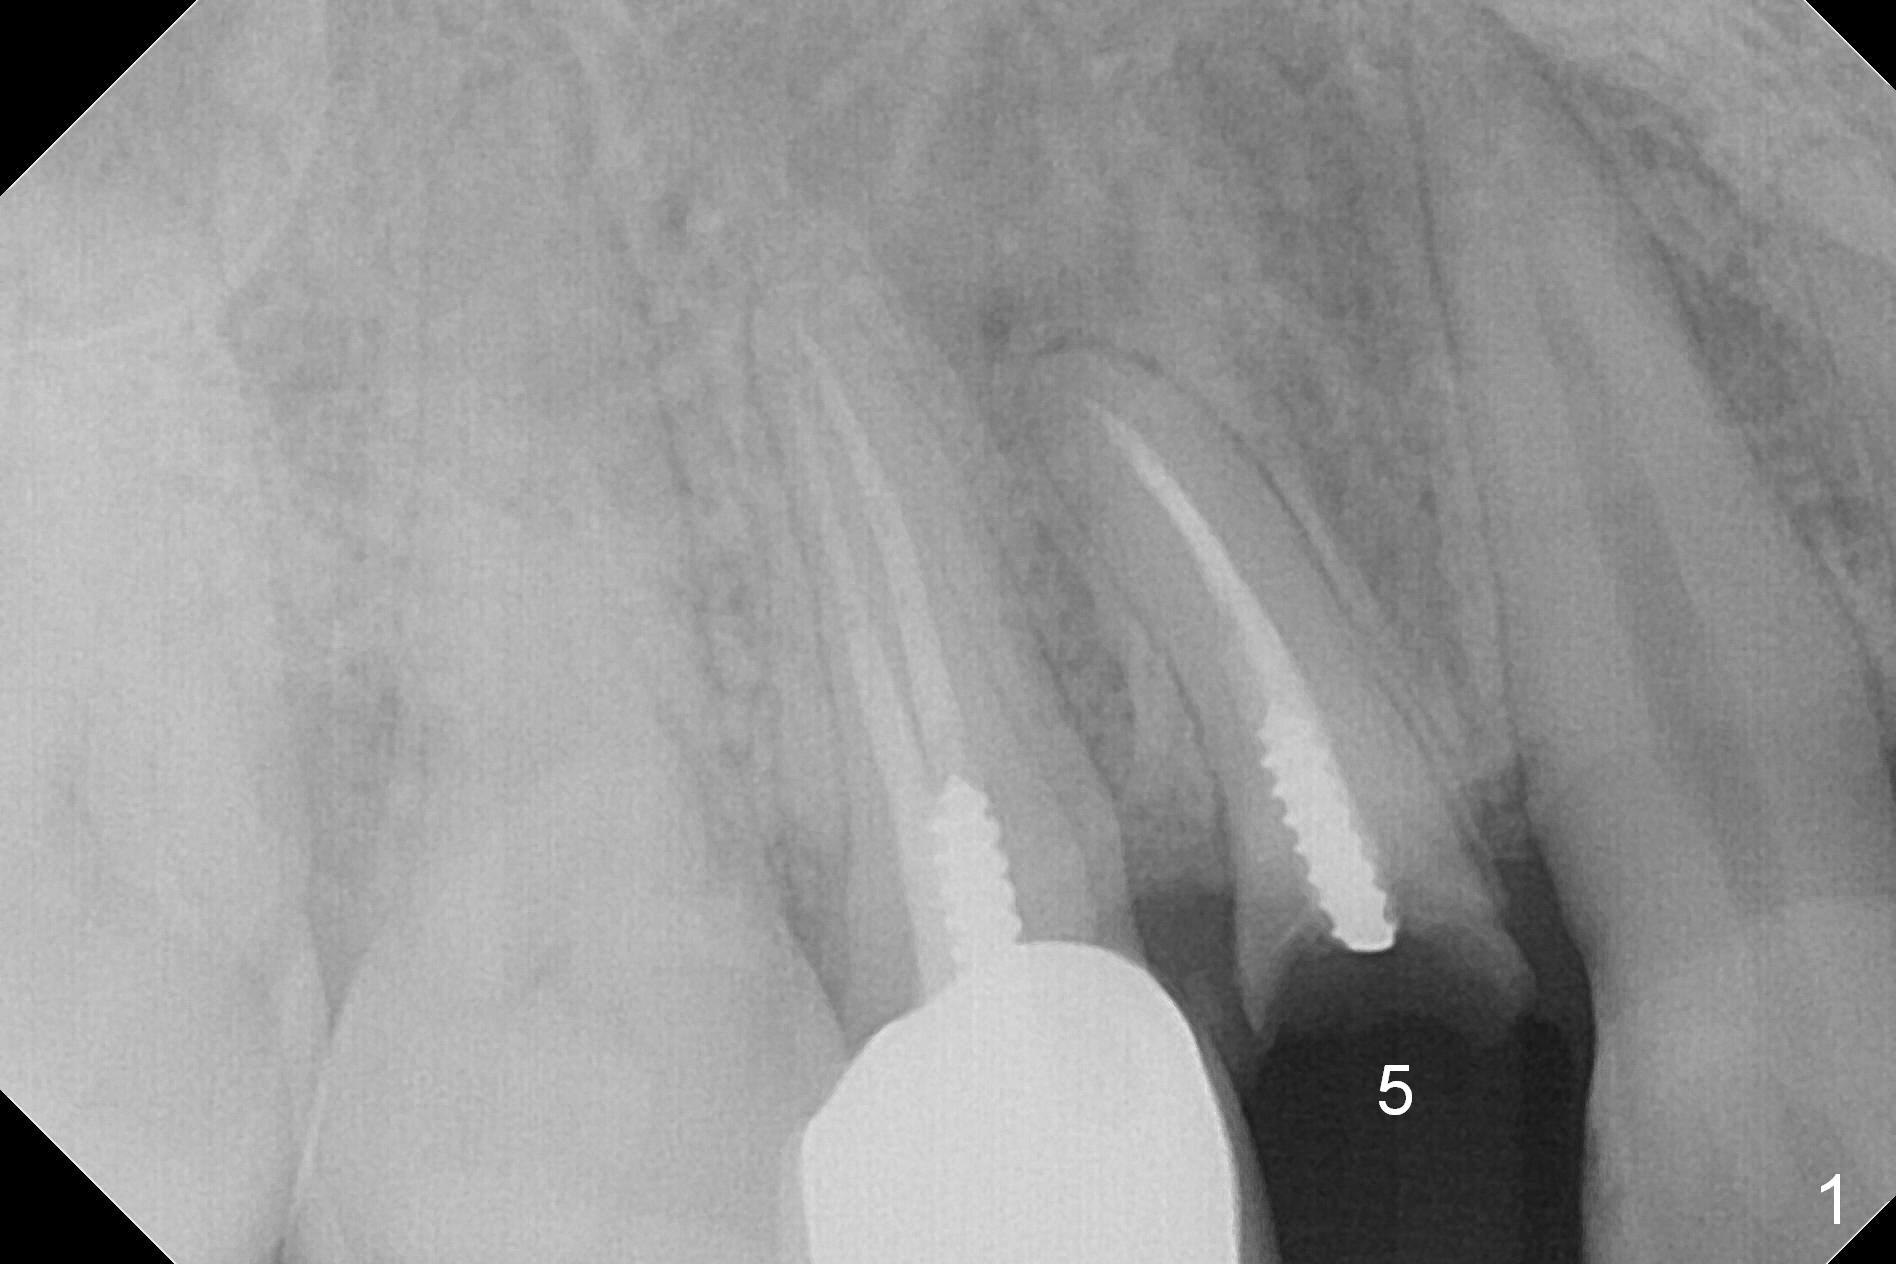

Curved Root

A 34-year-old man (smoker, half a pack a day) has residual root at #5 (Fig.1) with large periapical radiolucency (Fig.2 red dashed line). Since the root curves distally (Fig.3 black area, Clindamycin), osteotomy will be established in the mesial wall (red long arrow). A 3.8x16 or 18 mm implant is to be placed for primary stability (Fig.4). To reduce periimplantitis associated with smoking, place the implant deep. The implant appears to have better surface treatment. Pack sufficient bone graft and membrane. Immediate provisional should have good seal. To place the implant deep, osteotomy will be attempted with a long 1.5 mm pilot drill (PA), followed by 2 mm one with extension and 3.0x18 mm drill.